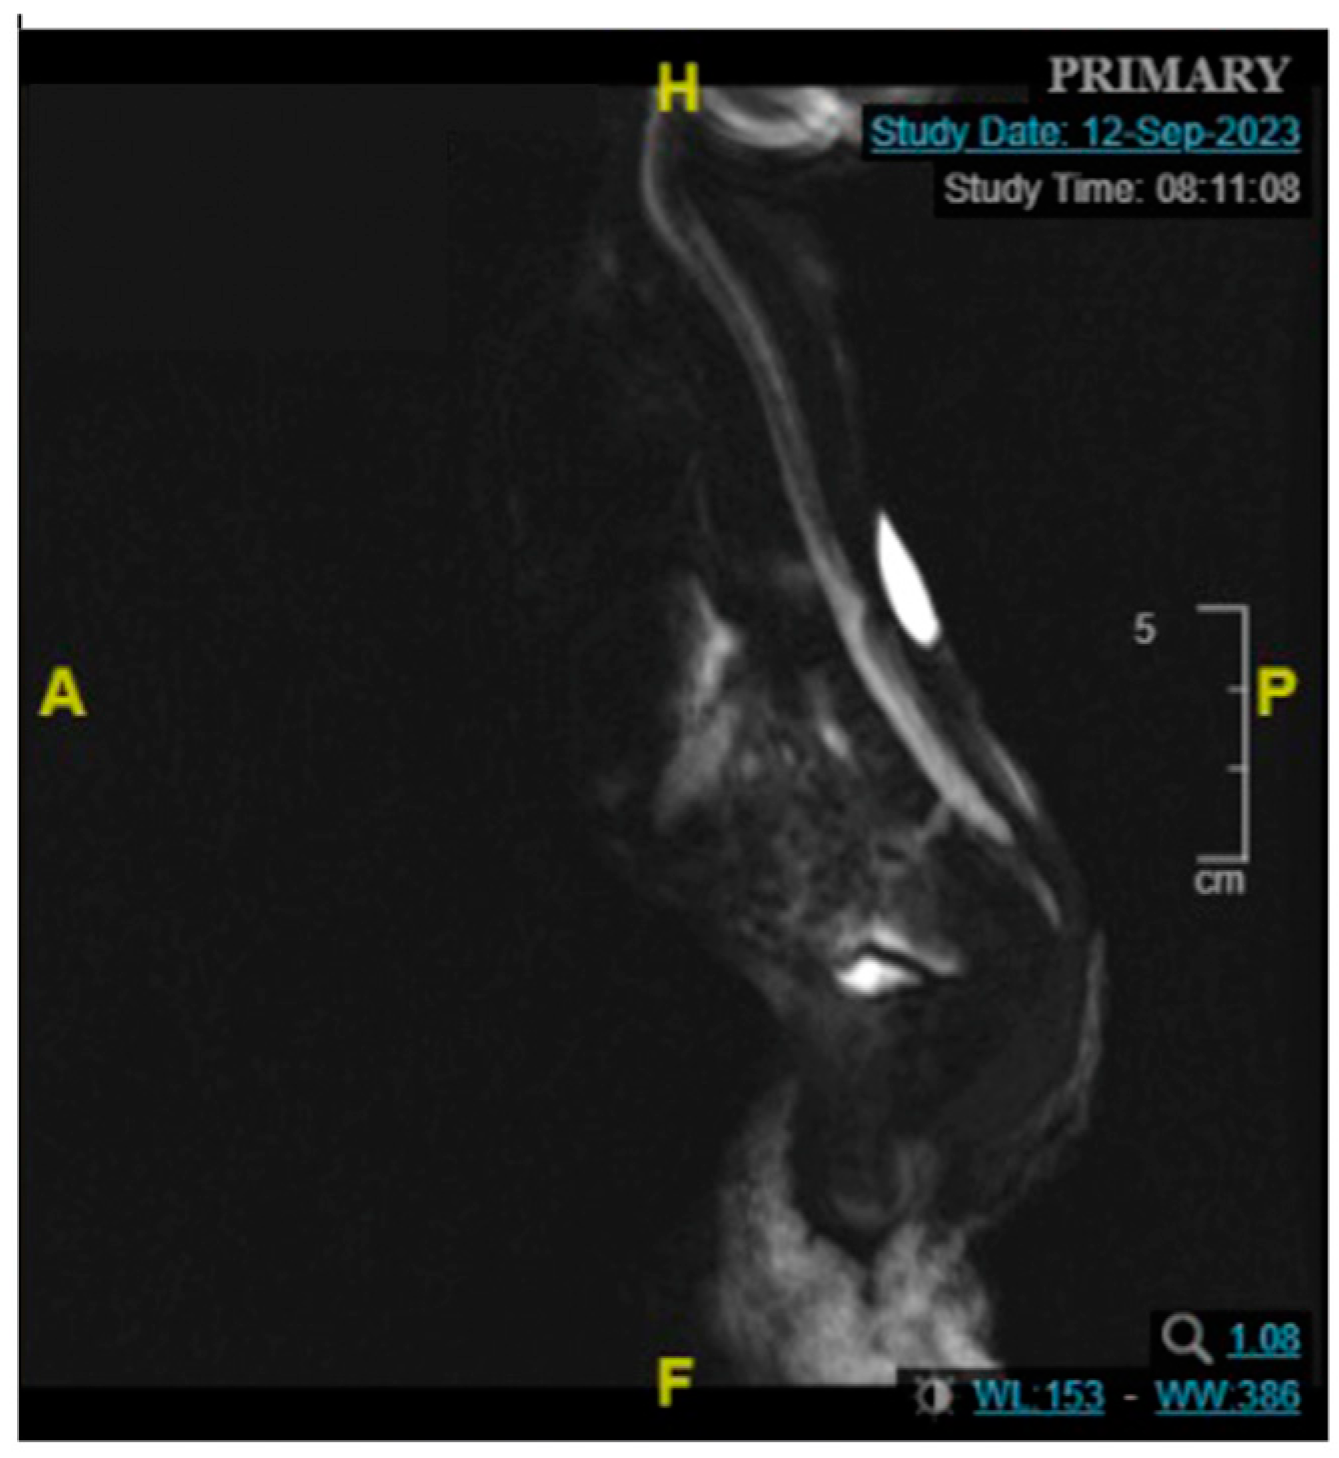

2.1. Patient 1